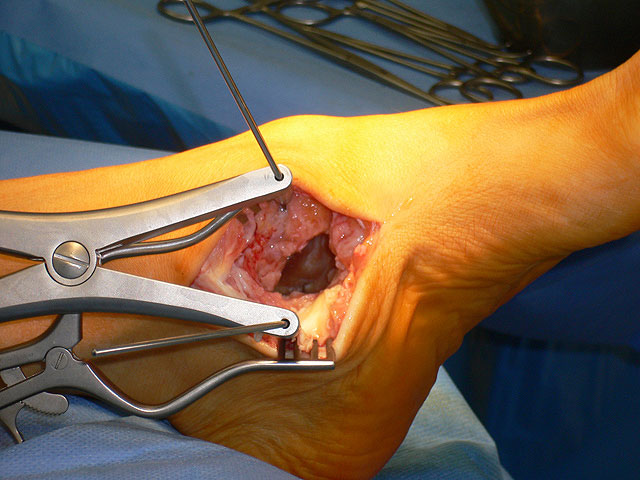

Je nach Operationsziel wird die Arthrodese des Subtalargelenks in verschiedenen Modifikationen durchgeführt. Ist der Rückfuß orthograd ausgerichtet, so erfolgt sie als in situ Fusion, d.h. ohne Korrektur Änderung der Rückfussachse. Liegt eine Rückfuß-Fehlstellung vor, kann diese durch ein additives oder substraktives knöcherndes Vorgehen korrigiert werden 12. Die Fixation der Arthrodese erfolgt üblicherweise mit (kanülierten) Schrauben die über den Tuber calcanei eingebracht werden 3. Eine zweite Schraube zur Sicherung der Rotationsstabilität wird optional über den Processus anterior calcanei im Talushals verankert 4. Der am häufigste verwendete Zugang zum unteren Sprunggelenk verläuft lateral subfibular, alternative Zugänge sind medial oder posterior möglich 56. Ist keine relevante Korrektur notwendig kann der Eingriff auch arthroskopisch durchgeführt werden 78.

Abbildung 1

Abbildung 2

Eine unzureichende Präparation des Gelenks ohne Aufbrechen des subchondralen Sklerosezone erhöht das Risiko der Pseudarthrosenentwicklung 2.

Eine Coalitio der medialen Gelenkfacette kann das operative Vorgehen erschweren. Das Gelenk läßt sich nicht öffnen, wird es mit Gewalt aufgehebelt können unkontrollierte Bruchlinien in Kalkaneus und Talus entstehen. Liegt eine Coalitio der medialen Gelenkfacette vor, die meist mit einer Rückfußvalgusstellung vergesellschaftet ist, hat sich ein medialer Zugang bewährt über den die Coalitio reseziert und der Rückfuß in Closing-wedge Technik korrigiert werden kann 1617.